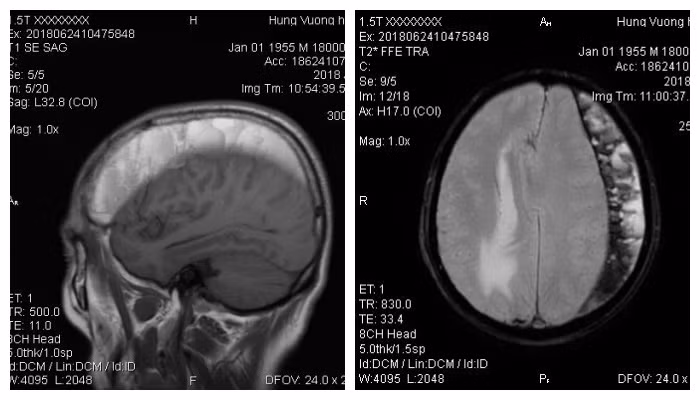

Bệnh nhân được chỉ định làm cận lâm sàng cần thiết. Kết quả cho thấy, bệnh nhân bị tụ máu dưới màng cứng bán cầu đại não trái, cần được phẫu thuật ngay.

Một số chấn thương mạn tính như máu tụ dưới màng (trường hợp của bệnh nhân S.) sẽ xuất hiện triệu chứng đau đầu kèm yếu nửa người, suy giảm trí nhớ, buồn nôn.